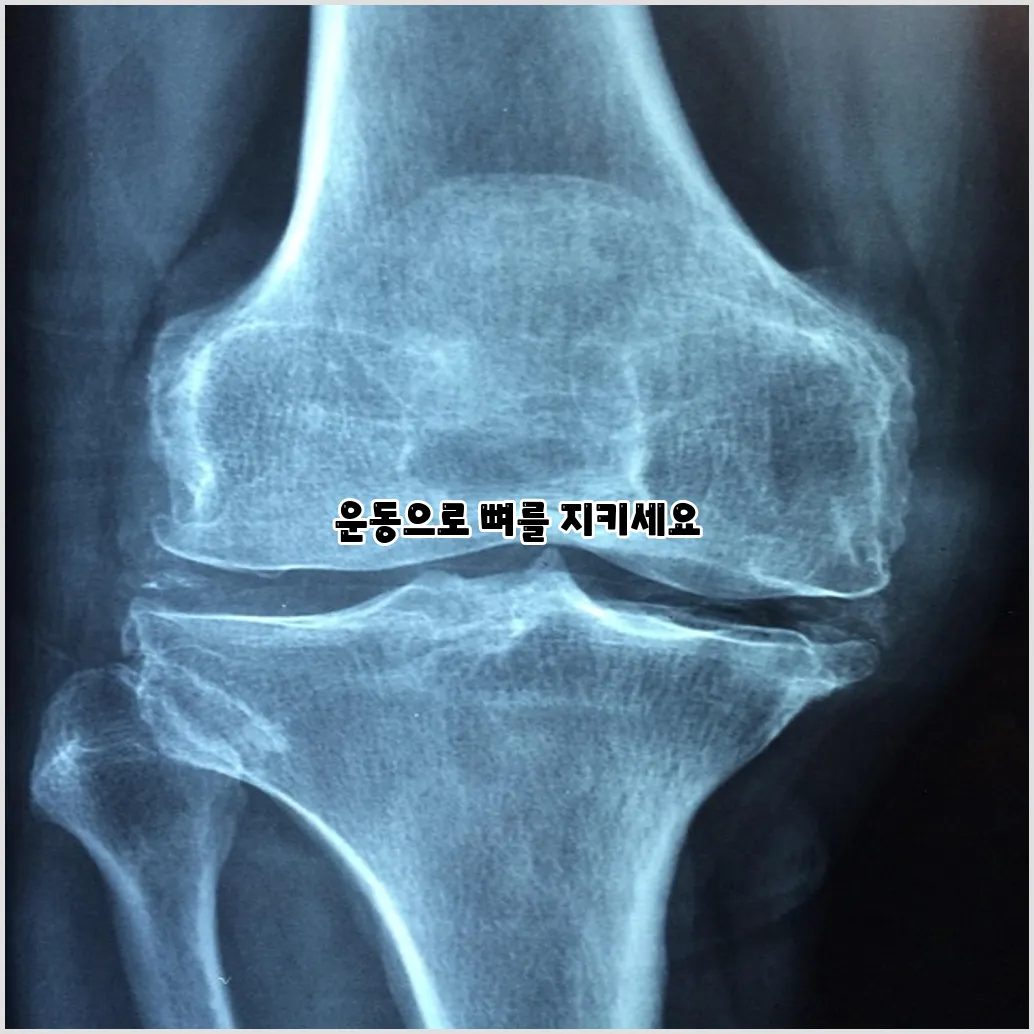

골다공증은 뼈의 밀도가 감소하여 뼈가 약해지는 상태를 말합니다. 이러한 상태는 골 fracture의 위험을 증가시킵니다. 실제로, 골다공증 예방은 단순히 뼈의 건강을 유지하는 것만이 아닌, 삶의 질을 높이는 데 있어서도 매우 중요합니다. 뼈 건강을 위해 가장 먼저 떠오르는 것이 바로 균형 잡힌 식단입니다. 하지만 운동 또한 중요한 역할을 합니다.

골다공증은 특히 노인에게 큰 문제를 일으킬 수 있습니다. 뼈 밀도가 낮아지면 작은 충격에도 쉽게 골절이 발생할 수 있기 때문입니다. 골다공증 예방을 위해서는 조기 진단과 정기적인 운동이 중요합니다. 매일 운동을 하는 습관을 기르면 뼈의 건강을 유지하는데 큰 도움이 될 것입니다.